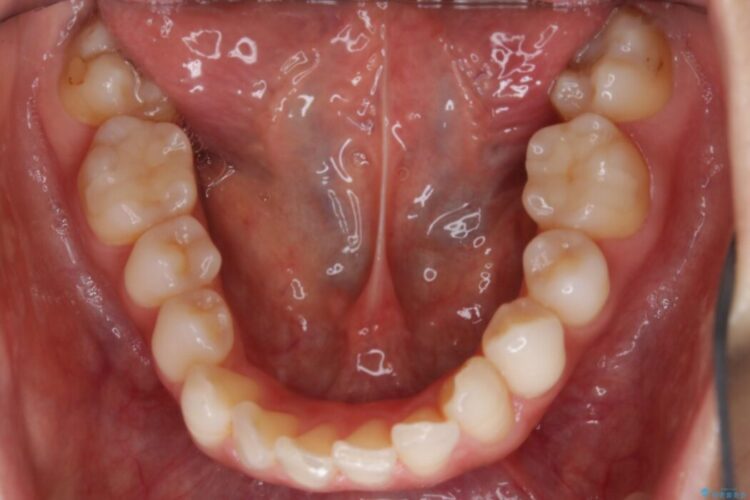

軽度のガタつきと不正咬合が見受けられましたので、インビザラインでの矯正治療を計画しました。

既定のインビザラインの装着時間を守っていただけたこともあり整ったアーチとなりました。

特に気にされていた噛み合わせは改善されご満足いただけました。